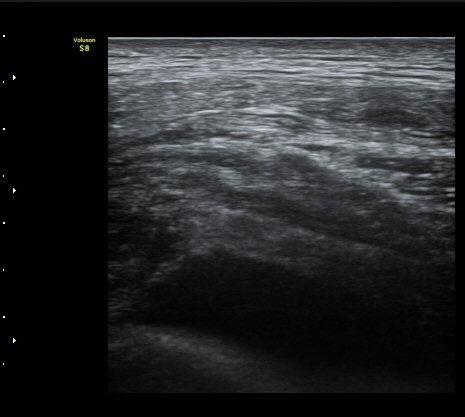

°¥ºñ»À °ñÀý ÈÄ Å« ÀüÀ§°¡ °üÂûµÊ(fracture with displacement) »çÁø 3